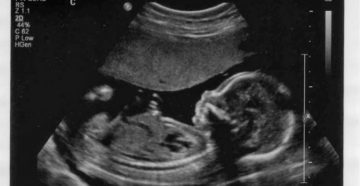

Патология пуповины плода ■ изменение длины (абсолютная и относительная короткость); ■ наличие узлов пуповины (истинные…